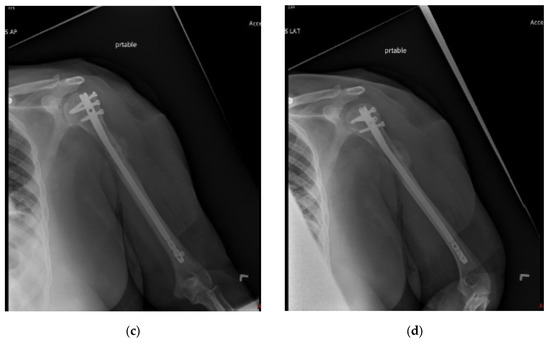

Figure 3.

(a) AP and (b) oblique left humerus radiographs of a 47-year-old female with mixed lytic sclerotic lesion in the proximal meta-diaphyseal region, with a pathologic fracture and periosteal reaction in a patient with established metastatic breast cancer. This was treated by an uncemented IMN, with three proximal locking screws and one distal screw, as shown in (c) AP and (d) oblique humerus radiographs. No cement was used, as there was enough proximal and distal bone to support the nail and the inter-locking screws, and some healing changes were already evident.